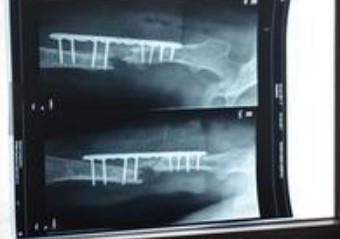

乡亲们把老人拉到商洛市第二人民医院。一番检查后花光了老人仅有的900元积蓄。医院查明了老人的骨盆和右髋骨之间有一个近五厘米的线性金属异物,而这个异物是几十年前的老式注射器针头,伤及老人的坐骨神经,所以老人不能动弹了。因无钱做手术,乡亲们只好把老人拉回家,由亲戚照料。

商洛市第二人民医院1月28日检查显示:拍的片子上能够清楚看到这个针头,扎在骨头里的部分也看得清清楚楚。这个针头到底是如何进入老人体内的?陈继善说,早在20多年前,他得了一次肺气肿,先后在村上的卫生站和商州区医院治疗,打过肌肉针,起了一个大包,后来疙瘩也不见了,此后他再没打过针。在哪儿留下的针头,老人记不清了。